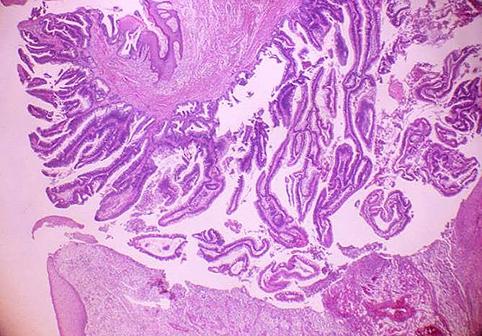

疾病(病理主体)的分类恶性上皮性肿瘤/腺癌

部位(按器官分)大肠/盲肠

检查方法病理切片(微观)

肿瘤的肉眼分类1型(肿瘤型)/

肿瘤最大直径40以上

肿瘤的深度s(a)